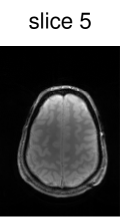

To verify the in-vivo applicability, human brain images of a healthy volunteer were acquired using the above described GRE sequence modified to include the optimized CAIPIRINHA-based pulses. The sequence parameters were set to , , bandwidth , matrix size and FOV . After acquisition, the k-space data of the individual slices were separated using an offline slice-GRAPPA ( coils, kernel size of ) reconstruction [42, 9]. The reference scans used in the slice-GRAPPA reconstruction were performed with the same sequence using an optimized single-slice pulse (not shown here). To decrease the scanning time, we acquired k-space lines ( of the full dataset) around the k-space center for each reference scan. After this separation, a conventional Cartesian reconstruction was performed individually for each slice.

Figure 6 shows the image reconstruction using optimized RF pulses for simultaneous excitation of two, four and six slices with the same slice separation and thickness as above. As can be seen clearly in the first column, all three pulses lead to the desired excitation pattern in-vivo as well. The remaining columns show the slice-GRAPPA reconstructions, which illustrate that the excitation is uniform across the field of view.